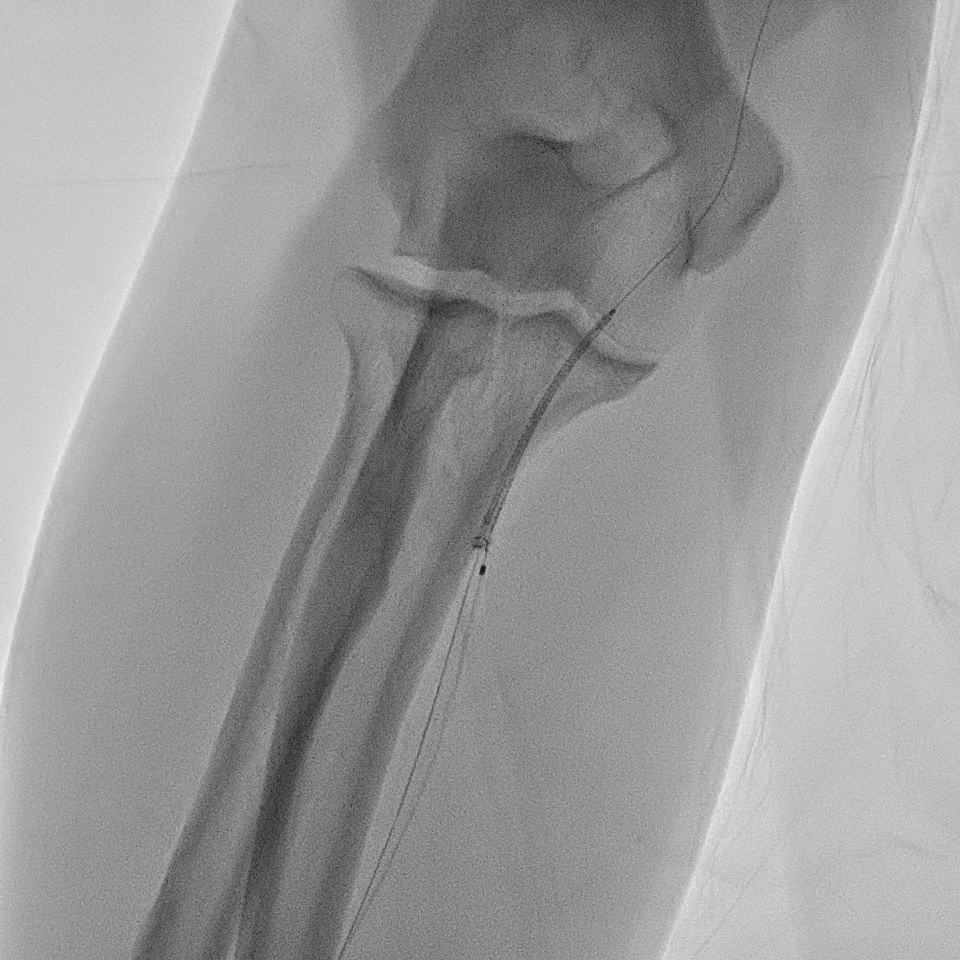

A right radial artery approach with 6Fr sheath was used. The right coronary system was engaged with 6Fr Judkin Right (JR4) guiding catheter. The posterior left ventricular branch was wired with Runthrough NS. Intravascular ultrasound (IVUS) showed distal RCA landing zone vessel size of 4.0-4.5mm in diameter. The mid RCA showed minimal luminal area (MLA) of 1.95mm2 with fibrous plaque and calcification at 12 o'clock. The proximal RCA landing vessel size was 4.5-5.0mm in diameter. The lesion was predilated with NC Trek Neo balloon 3.0x15mm. Attempted multiple times to deliver the stent SYNERGY 4.0X48mm but failed. The stent could not be passed into proximal RCA and eventually the distal stent edge crimpled and unable to be withdrawn into the guiding catheter. Tried to pull back system enbloc into the radial artery. Attempted to pull the stent into guider but failed again. The guiding catheter was removed. The stent was left with coronary wire in situ. Exchanged 6Fr radial sheath to slender sheath and attempted to snare stent with 2.0mm snare but failed. Attempted multiple wire wrapping technique with 3 BMW wires but failed. Decided to puncture right femoral artery with 8Fr sheath. A 7Fr JR4 guiding catheter was introduced into right brachial artery. A 7mm snare then snared the stent and removed it via femoral. The lesion was predilated with Scoreflex 3.5x20mm, stented with Supraflex Cruz 4.0x48mm and post-dilated with NC balloon 4.5mm. Result was TIMI 3 and no dissection.

Case Summary